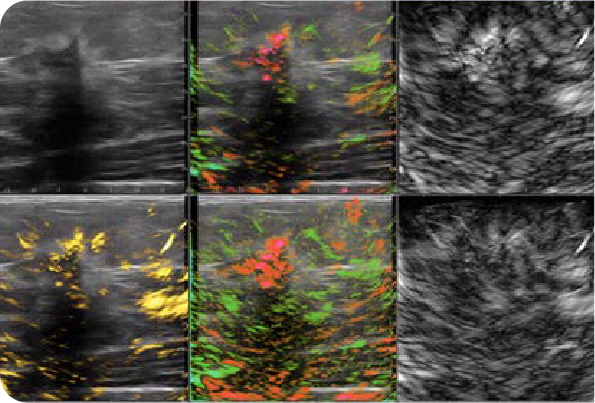

Pioneered by Seno Medical, Opto-Acoustic/Ultrasound (OA/US) shines a new light on breast cancer diagnostics, enabling a real-time assessment to differentiate malignant from benign breast tissue.

Without dyes, radiation, or invasive procedures, Imagio® provides the clinician an immediate, objective diagnosis leveraging the AI-driven clinical decision support tool, SenoGram®.

See Imagio® and SenoGram® in action with a clinical demonstration of OA/US technology and examples of images that can differentiate malignant and benign breast tissue on screen and in color, with the painless, real-time OA/US scan.